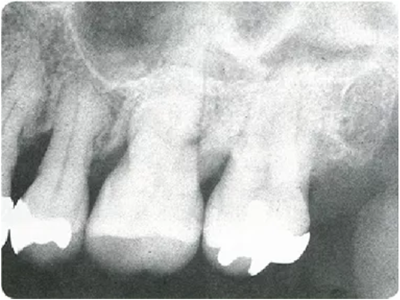

探針在牙周袋內(nèi)的工作方式

~步行式探診~

牙周探診在掌握眼睛看不到的部分的狀態(tài)方面,是非常重要的一個檢查。參考X片進(jìn)行探診,可以立體掌握該檢查部位。

然而X片中無法看到所有信息。魚食,牙周探針的工作尖需要像步行一樣在袋底走動運用步行式探診法可以更準(zhǔn)確掌握該部位的狀況。

● 僅有X片,無法掌握到牙周袋底的狀況嗎

此時運用的牙周探診技巧稱為“步行式牙周探診法”。

2、一定要變看X牙片

邊進(jìn)行牙周探診

牙周病即使是在同一口腔內(nèi),每顆牙齒、牙齒的每個面惡化程度都不相同,有部位特異性。因此,牙周病的檢查不是要看全體的進(jìn)行程度,而是有必要對逐個面、逐個點進(jìn)行檢查。

如果在對哪個部位進(jìn)行到什么程度沒有預(yù)想的狀態(tài)下進(jìn)行探診,由于復(fù)雜的根面形態(tài)和牙周狀態(tài),無法正確插入探針、被牙結(jié)石擋住、遺漏等就很容易發(fā)生。

因此,在檢測牙周袋深度時,通過 X 片確定牙槽骨的狀態(tài)、根的形態(tài)、牙結(jié)石的附著狀態(tài)等,在腦中有一個大致的印象,應(yīng)該可以很大程度上減少漏檢。

僅通過口腔視診是無法看出何處有骨吸收的。通過拍攝的牙片,可以一定程度上掌握牙槽骨吸收的情況。

如果觀察X片后預(yù)想的狀態(tài)和牙周探診分析出的狀況有很大差異,就需要再次注意此部位并重新做一次牙周探診。